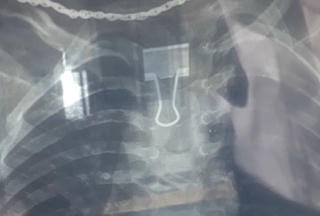

từ khóa: #kẹp giấy